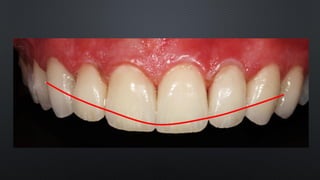

• OVERBITE OU SOBREMORDIDA

RELAÇÃO ENTRE ARCOS

TRESPASSE VERTICAL

• REFERE-SE AO QUANTO OS INCISIVOS SUPERIORES COBREM NOS INFERIORES

• APROXIMADAMENTE 30%

• OVERBITE OUSOBREMORDIDA RELAÇÃO ENTRE ARCOS TRESPASSE VERTICAL • REFERE-SE AO QUANTO OS INCISIVOS SUPERIORES COBREM NOS INFERIORES • APROXIMADAMENTE 30%